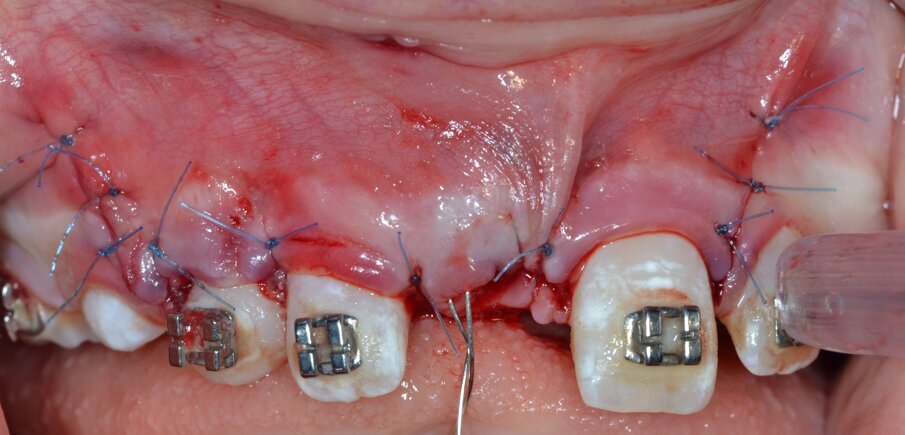

Si procede all’esecuzione dell’alveolectomia conduttrice (Figg. 14, 15) allo scopo di facilitare la trazione ortodontica mediante inserto dedicato montato su dispositivo piezoelettrico (ES009ST Esacrom Srl, Imola, Italia) e, successivamente, all’adesione del bracket ortodontico sulla corona dell’elemento 1.1 (Figg. 16, 17). L’ ultimo tempo operatorio prevede il riposizionamento e la sutura del lembo (Fig. 18) con punti staccati in Nylon 5/04 seguito dal riposizionamento in sede del filo ortodontico (Fig. 19).

Fig. 18_Riposizionamento del lembo e sutura con filo in Nylon 5/0.